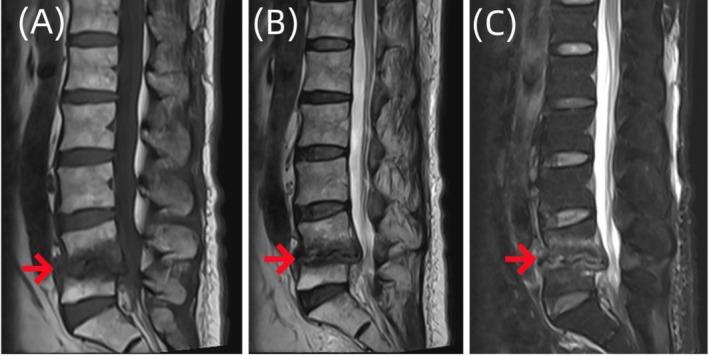

Suppurative Spondylitis Misdiagnosed as Endplate Inflammation: A Rare Case Report.

Spinal infectious diseases are difficult to diagnose and treat; we reported a case of pyogenic spondylitis misdiagnosed as terminal discitis and successfully treated. The application of metagenomic next-generation sequencing technology holds promise in greatly improving diagnostic efficiency.